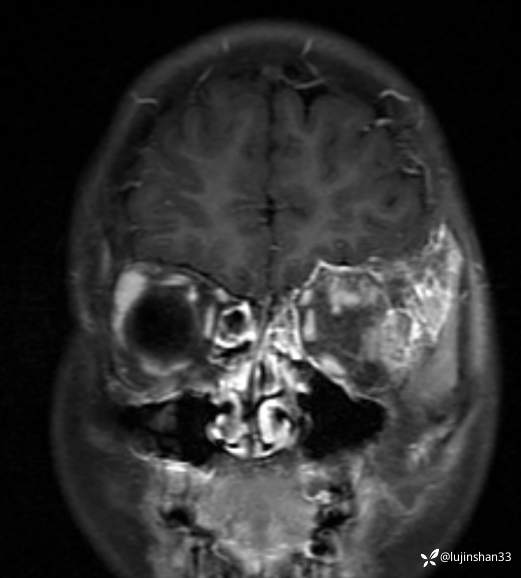

简要病史:患儿父母半年前发现患儿左颞部较右侧突起,无伴随症状,未重视未诊治,1月前,患儿左颞部肿物长大,伴头晕,向一侧倾倒感,头痛,两次剧痛,余为胀痛,偶有夜间出现左下颌区域皮肤麻木,咀嚼时左面部疼痛,10天前,患儿出现左眼睑肿胀伴疼痛,睁眼疼痛加重,不伴视力障碍,无畏寒发热,无意识障碍,无饮水呛咳,在XX同仁医院行颅脑核磁示:左侧颞下窝占位。门诊以“颞下窝占位(左)”收入院。患者目前精神状态良好,体力正常,食欲正常,睡眠正常,体重无明显变化,大便正常,排尿正常。

临床诊断:颅中窝、颞下窝小圆细胞恶性肿瘤

2021年8月复查MRI